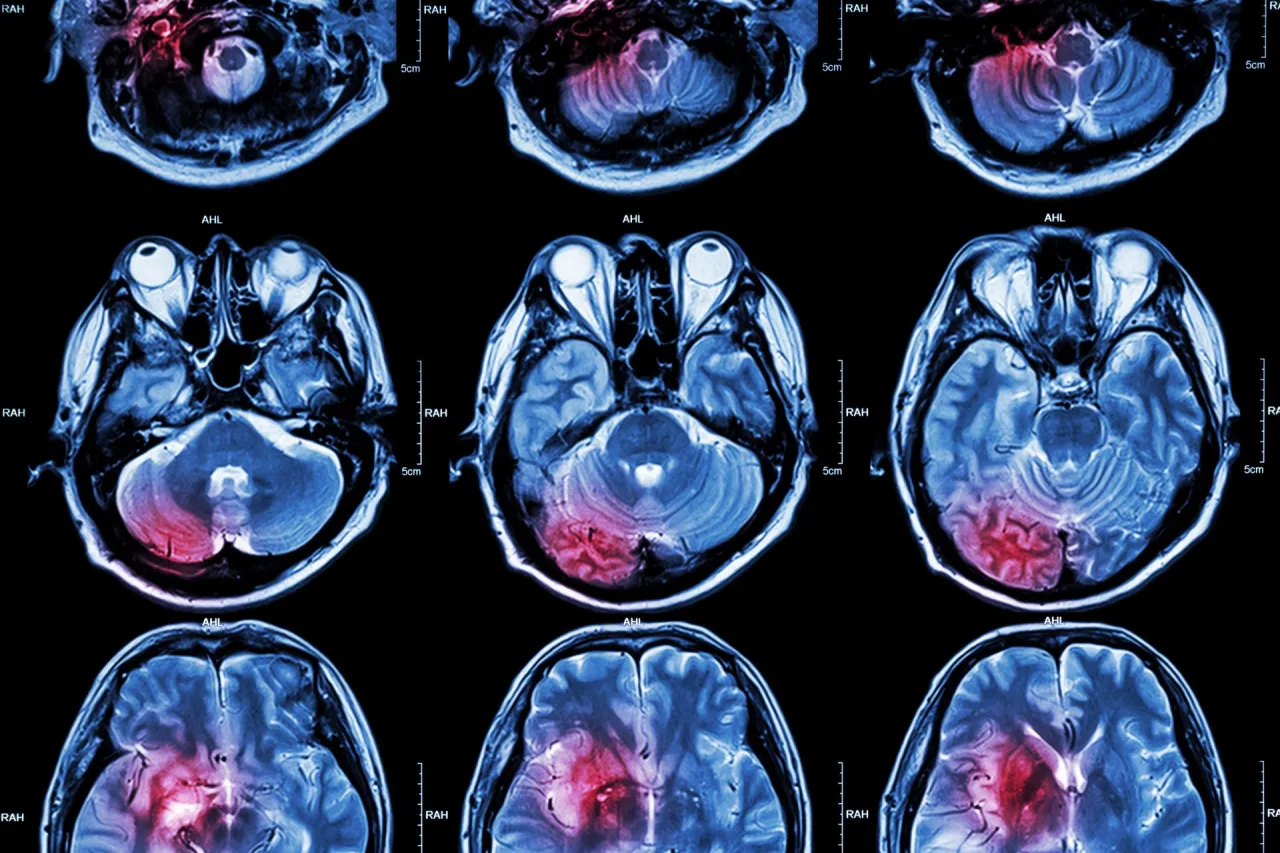

Stopień uszkodzenia mózgu a możliwość pracy

Stopień uszkodzenia mózgu to jeden z najważniejszych czynników wpływających na powrót do pracy. Im mniejsze uszkodzenie, tym większe szanse na odzyskanie pełnej sprawności. W przypadku poważniejszych urazów proces rehabilitacji może trwać znacznie dłużej, a powrót do pracy może wymagać dostosowania stanowiska.

Lekarze często przeprowadzają szczegółowe oceny, aby określić, czy pacjent jest gotowy do podjęcia pracy. Badania neurologiczne i testy funkcjonalne pomagają w podjęciu decyzji o dalszych krokach.